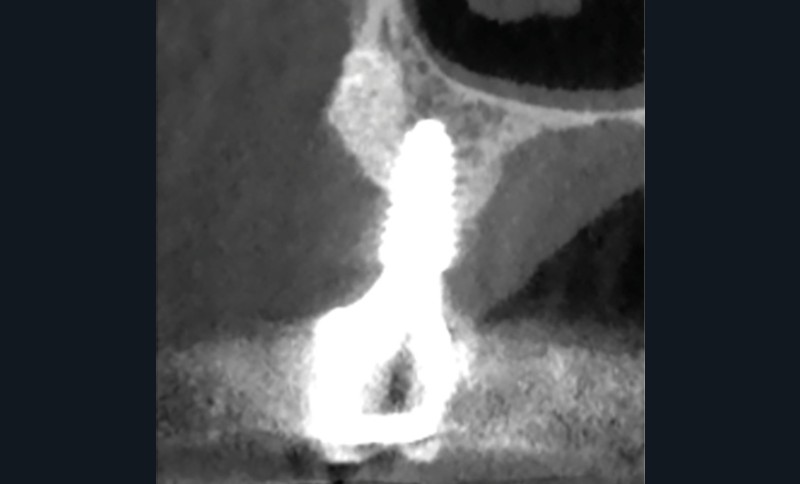

Il a d’abord été vérifié si un excès de ciment pouvait être à l’origine du problème, ce qui n’était pas le cas. Des irrigations locales avec du digluconate de chlorhexidine à 0,2 % ont été effectuées et la patiente a reçu pour instruction d’appliquer un gel à la chlorhexidine. Les symptômes ont disparu après deux semaines et l’examen CBCT a montré que l’os était sain (fig. 1b à d).